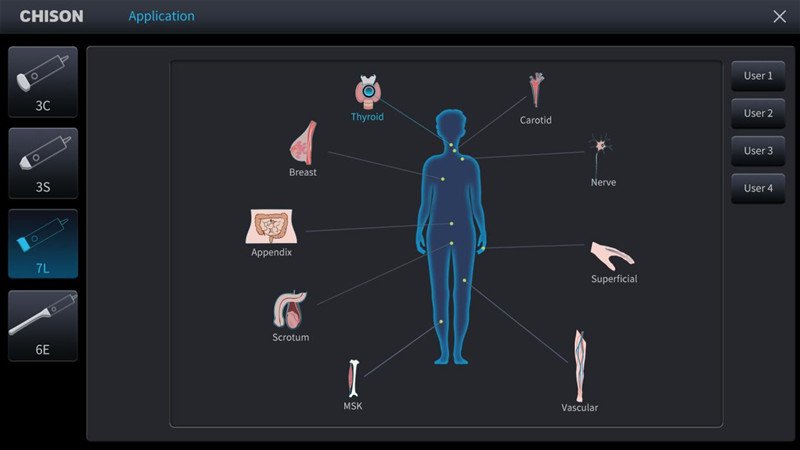

MSK ultrasound machines come with different transducer types, each designed for specific applications. Linear transducers are suitable for superficial structures and high-resolution imaging of tendons and nerves. Curvilinear or phased-array transducers are better for deeper structures like muscles and joints. Choosing a machine with multiple transducer options enhances its versatility for a wide range of MSK examinations.

An intuitive user interface and ease of use are critical for efficient workflow and accurate diagnosis. Look for features such as customizable presets, touch-screen capabilities, and user-friendly menus. A machine with advanced automation features, like image optimization and measurement tools, can further enhance productivity and streamline the imaging process.